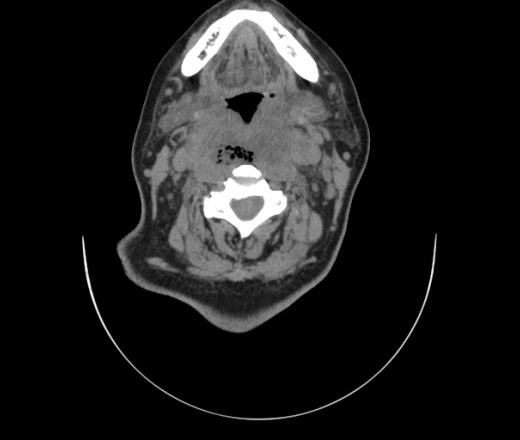

Женщина поступила в х/о спустя 4 дня после того как при употреблении карася подавилась костью.

Наличие газа в средостении на протяжении тел С2-С6 (медиастинальна эмфизема); рыбная кость на уровне тела С6.

При всем уважении, но говорить о медиастинальной эмфиземе, оценивая мягкие ткани шеи, как-то слишком резко. На мой взгляд, это ретрофарингеальное пространство.

Эвакуировали почти 100мл гноя. Но кость не смогли найти. Думаю что она даст дальнейшее ослоднение. Эндоскопически за черпалонадгортаной звязкой не смогли зайти в пищевод, все мягкие ткани отечные, просвет пищевода сдавлен. По всей видимости параэзофагеальная клетчака тоже задействована. Эмпиема, если ее можно так назвать, незнаю как правильно дошла до уровня яремной вырезки. Чем закончиться напишу. Ждем медиастинита.

Флегмона заглоточного пространства шеи, только операция, флегмоны вскрывают. Риск медиастинита.

Согласен с Вами; конечно, наличие газа в клетчатке ретрофарингеального пространства (затмение с опечаткой..). К сожалению, процесс "продвигается" к медиастиниту. Но почему никто, не отмечает наличие рыб. кости; или это для Всех очевидно?

Так вы уже отметили. Хотя ориентировал бы не скелетотопически, а на перстнечерпаловидный сустав.

Кость то мы сразу выявили, размеры где то 17*2мм, но ее так и не получается найти в этой каше